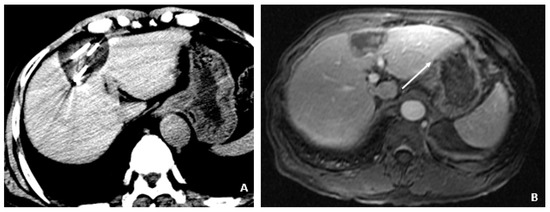

A 50-year-old male was diagnosed with CHB at age 40. With lamivudine treatment for 3 years, he achieved HbsAg seroconversion to anti-HBs and lamivudine was discontinued. Table 4 outlines his course. Five years later, on a follow up examination he was found to have HBV DNA 847 copies/mL, ALT 33 IU/L, and AFP 20.5 ng/mL. An MRI (December 2009) showed a 5 cm lesion consistent with HCC (Figure 1A,B). Repeat AFP was 17.8 ng/mL at time of HCC diagnosis, and AFP-L3% was 75.6. He underwent transarterial chemoembolization (TACE) with successful resolution (Figure 2A,B) and restarted lamivudine. The AFP remained at 3.0 ng/mL, and the MRI showed no evidence of HCC the following year. Two years after initial treatment, the AFP increased to 5.9 ng/mL with 57.5% L3. The MRI next month showed recurrent HCC at the treated site (Figure 3). The patient underwent laparoscopic radiofrequency ablation and therasphere treatment.

Figure 2.

Transarterial Chemoembolization (December 2009). (A) The selective left hepatic artery injection shows a blush of contrast corresponding to the hypervascular tumor (arrows). (B) An axial T1-weighted fat-suppressed portal-phase postcontrast MRI image 4 weeks following TACE shows lack of enhancement in the treated lesion with a small adjacent focus of necrosis (arrows).